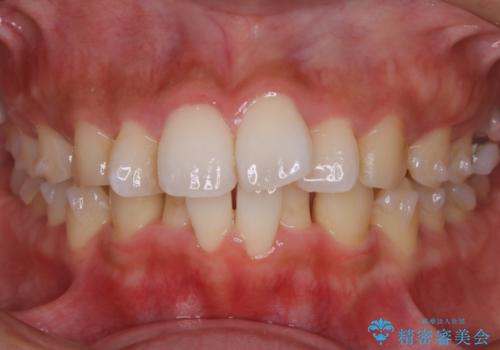

【非抜歯】インビザラインでガタつきと口元を改善!非抜歯でも印象が変わる矯正治療

- 歯のガタつきと口元の突出感を主訴に来院されました。

装置の希望がインビザラインだったため、非抜歯でインビザラインの特徴を最大限に生かして行う矯正治療を選択しました。

顔貌写真でも明らかに口の閉じやすさやEラインが改善している様子が分かります。